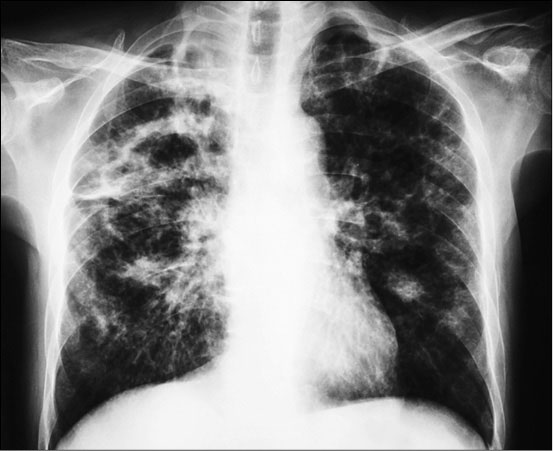

Рентгенограмма грудной полости больного туберкулезом

Возбудителем болезни является бактерия Mycobacterium tuberculosis. Инфекция передается воздушно-капельным путем. По оценке ВОЗ, треть всего населения планеты заражена микобактериями. Однако лишь у 5-10 % инфицированных со временем развивается туберкулез. В основном это люди, у которых по какой-то причине ослаблен иммунитет, или те, кто имеет генетическую предрасположенность к этой болезни. В последние десятилетия туберкулезом особенно часто заражаются ВИЧ-инфицированные люди, то есть люди, страдающие от иммунодефицита.